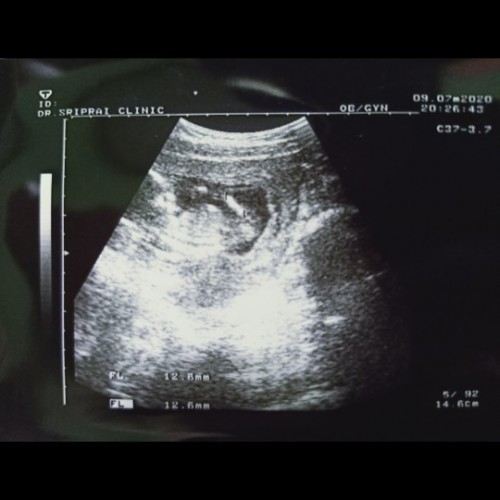

21 มกราคม ตอนนี้ 29w+1d ค่า